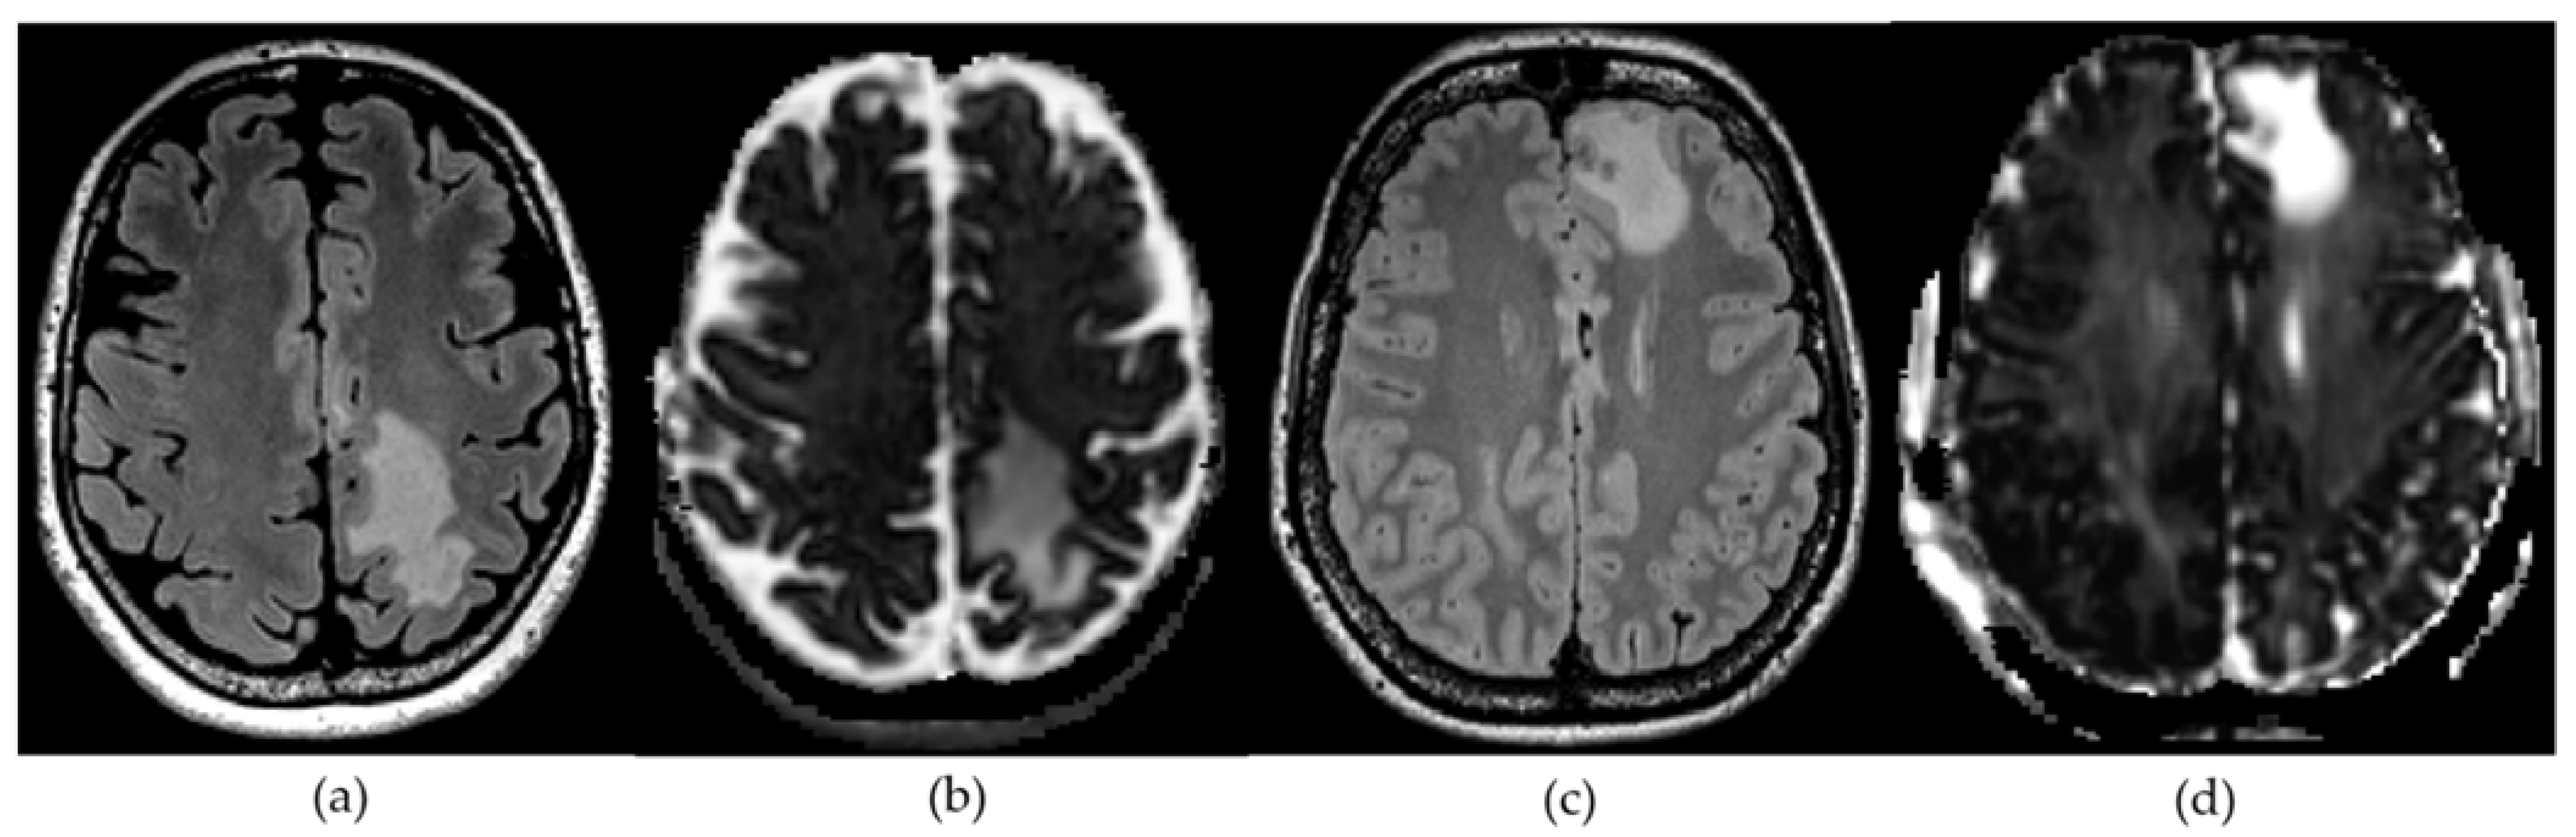

2.2. Diffusion Microstructure Imaging (DMI) and ROI Based Analysis